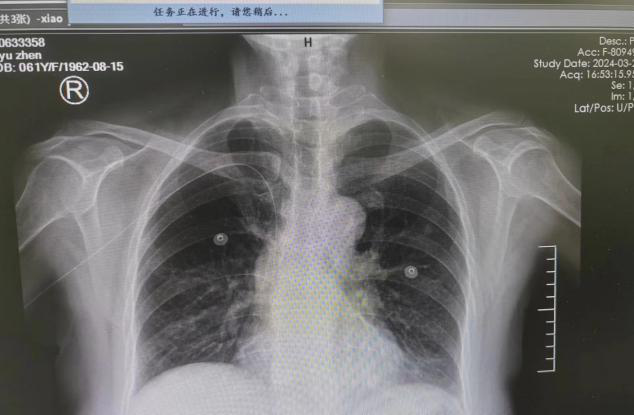

在沒有先例可循的情況下,護(hù)士長(zhǎng)邢善偉在B超引導(dǎo)下仔細(xì)查看血管,選定患者右上肢貴要靜脈,在端坐位的情況下為其進(jìn)行PICC置管術(shù)。經(jīng)過護(hù)理團(tuán)隊(duì)的通力協(xié)助,整個(gè)置管過程十分順利。在B超引導(dǎo)下,護(hù)理人員一針成功穿刺貴要靜脈,鞘管及導(dǎo)管均順暢送入,經(jīng)腔內(nèi)心電圖定位提示,成功將PICC導(dǎo)管尖端置于CAJ處。術(shù)后胸片定位示導(dǎo)管尖端位于上腔靜脈與右心房的連接處,標(biāo)志著腫瘤科首例坐位下PICC置管術(shù)大功告成。肖女士緊鎖的眉頭也舒展開來(lái),露出了滿意的笑容。